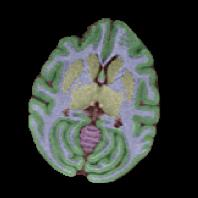

Non-human primates (NHPs) serve as critical models for understanding human brain function and neurological disorders due to their close evolutionary relationship with humans. Accurate brain tissue segmentation in NHPs is critical for understanding neurological disorders, but challenging due to the scarcity of annotated NHP brain MRI datasets, the small size of the NHP brain, the limited resolution of available imaging data and the anatomical differences between human and NHP brains. To address these challenges, we propose a novel approach utilizing STU-Net with transfer learning to leverage knowledge transferred from human brain MRI data to enhance segmentation accuracy in the NHP brain MRI, particularly when training data is limited. The combination of STU-Net and transfer learning effectively delineates complex tissue boundaries and captures fine anatomical details specific to NHP brains. Notably, our method demonstrated improvement in segmenting small subcortical structures such as putamen and thalamus that are challenging to resolve with limited spatial resolution and tissue contrast, and achieved DSC of over 0.88, IoU over 0.8 and HD95 under 7. This study introduces a robust method for multi-class brain tissue segmentation in NHPs, potentially accelerating research in evolutionary neuroscience and preclinical studies of neurological disorders relevant to human health.